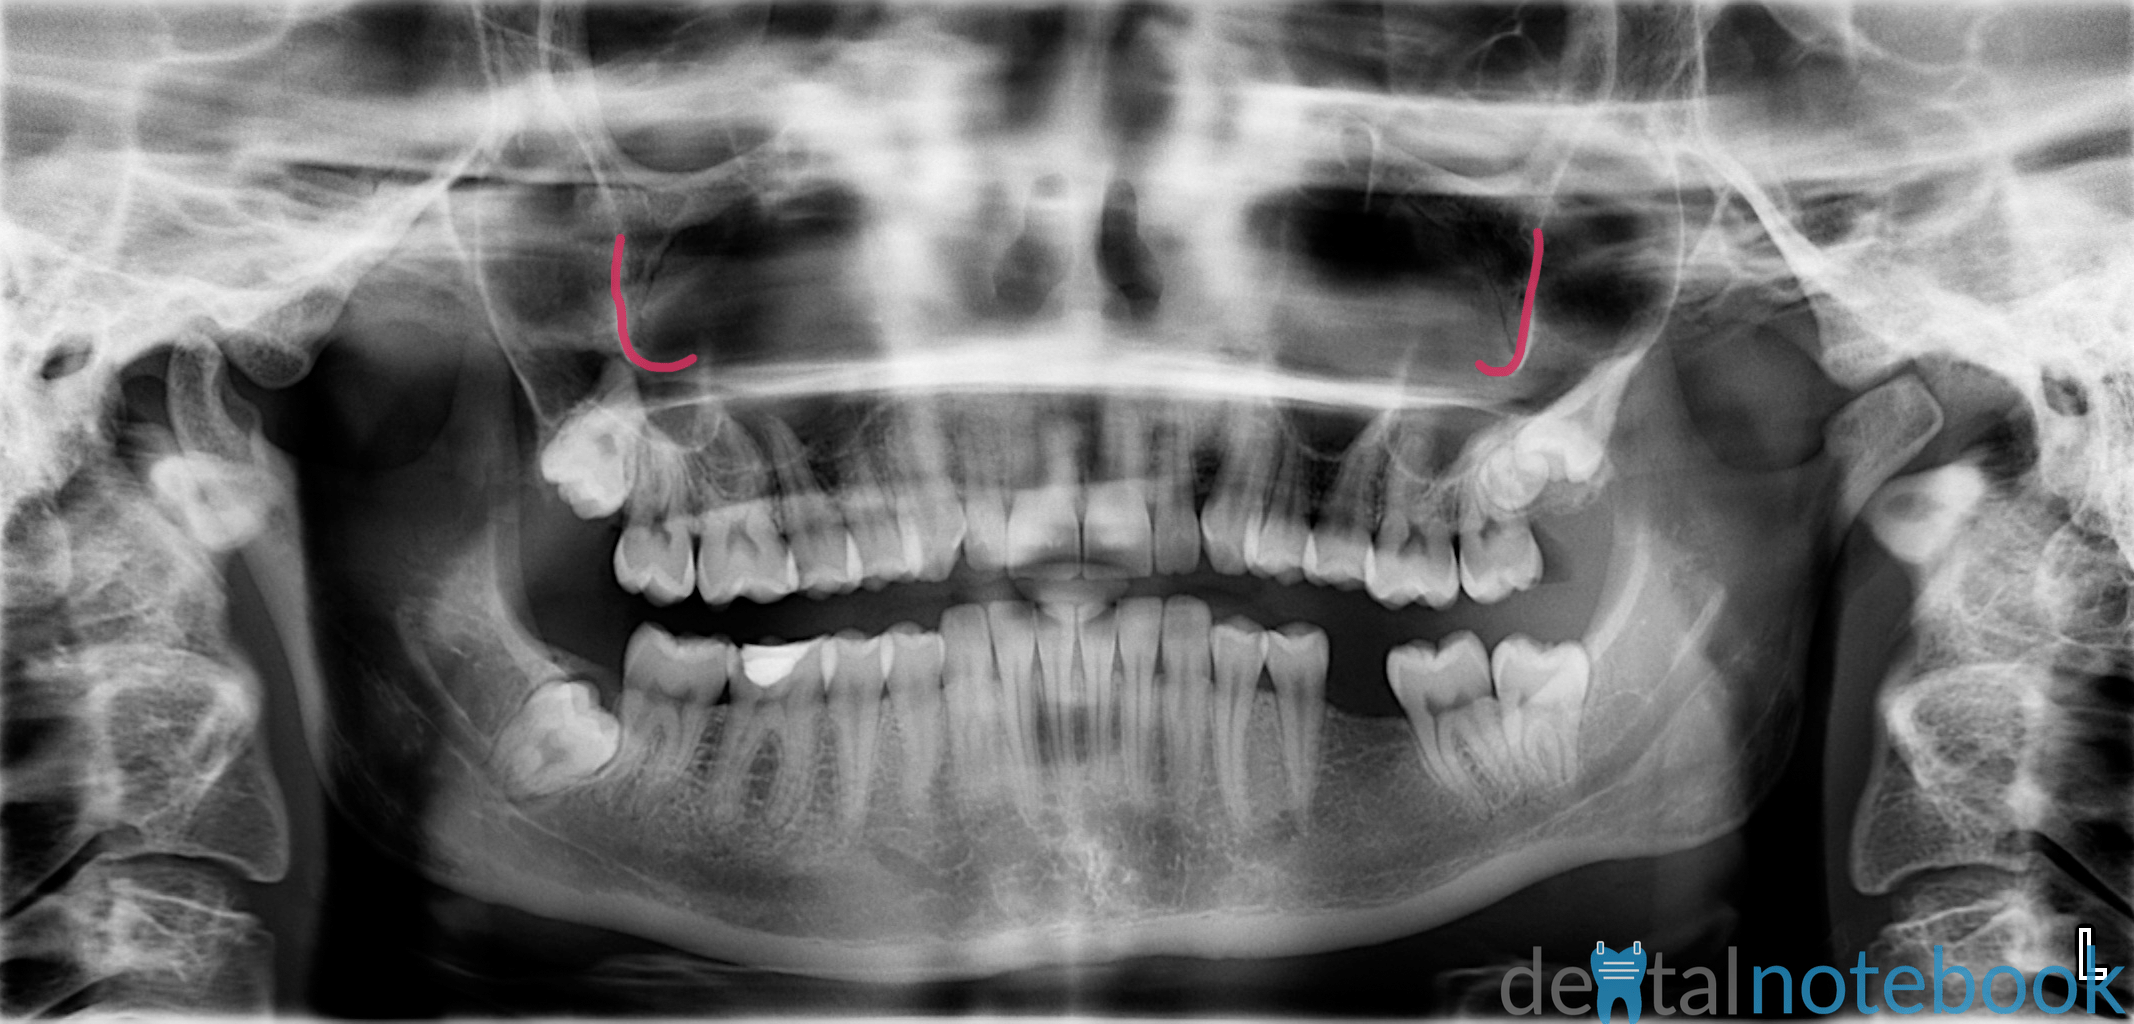

Anatomy of Panoramic Films OPTs/DPTs/OPGs dentalnotebook Zygoma Dental X Ray Position head so that chin is resting on table. The zygomatic bone (also known as zygoma or malar bone) is an important facial bone that forms the prominence of the cheek. The zygomatic bone can be seen on maxillary. The zygomatic bone, quadrangular in shape, broadens as it extends posteriorly. Read about different projections used in face and mandible Learn. Zygoma Dental X Ray.

From www.dentalnotebook.com